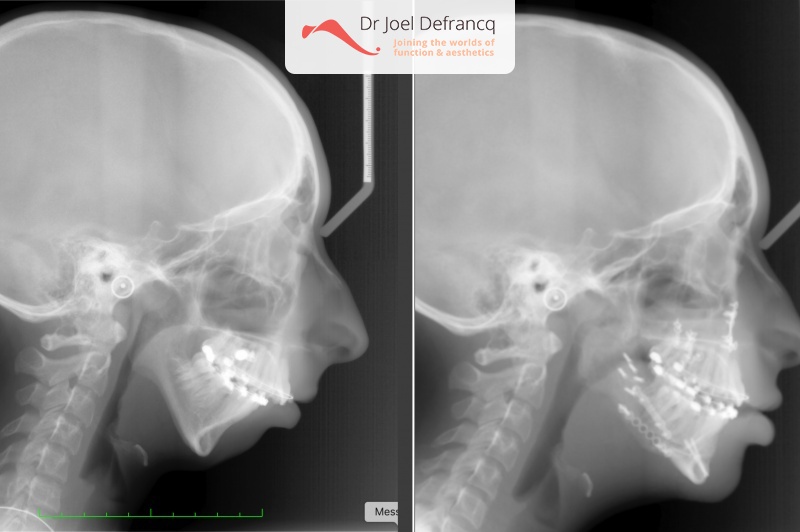

Nora: Kaakhoek augmantatie / Cone opbouw / Wrap around / Peek implantaten / PSI

Kaakchirurgie

- Verlenging onderkaak (BSSO)

- Verlenging bovenkaak (Le Fort I)

- Kinchirurgie

- Verbreden bovenkaak (Smile distractor)

- PEEK implants werden gecreëerd 8 maanden na de trimax.advacement osteotomies